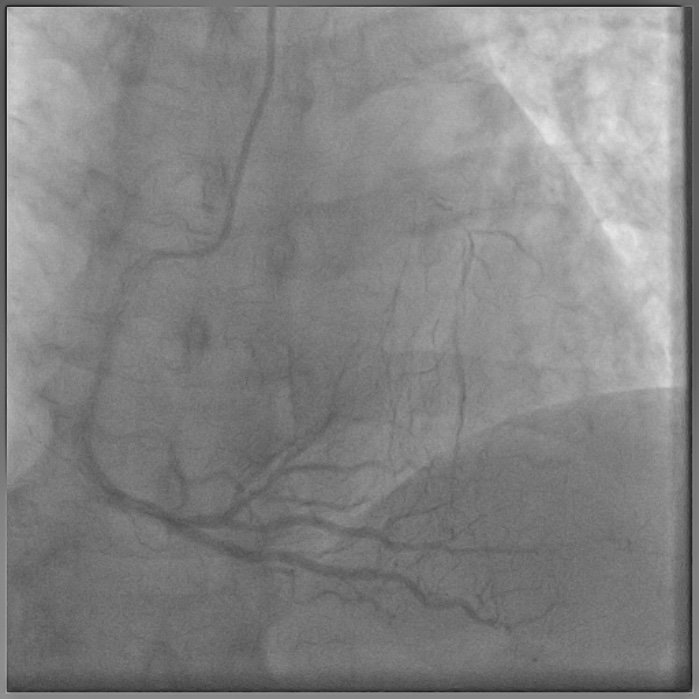

8F JL coronary guide catheter was taken from the right femoral artery and a TIG diagnostic catheter was taken from right radial artery and bilateral angiograms were taken. A floppy guide wire was placed in Lcx and ostial Lcx lesion was predicated with a 2*12 mm non compliant balloon. An IVUS catheter was placed over Lcx wire and under IVUS guidance a Gaia 3 coronary wire (Asahi, Japan) over a micro catheter was used to probe the ambiguous osmium of LAD (T1). Using contralateral injection in RCA, the Gaia 3 wire was seen extending into the false lumen in distal LAD. A Conquest Pro 12 (Asahi, Japan) was then taken over a micro catheter using a parallel wire strategy and successfully negotiated in distal true lumen of LAD (T2). After pre dilatation of LAD, Conquest Pro wire was exchanged for a floppy guide wire over a micro-catheter. IVUS run was then taken from LAD to LM and LCx to LM for vessel sizing. In view of the discrepancy in size of LAD/LCx and LM, 2 coronary stents were placed in a V technique from LM to LAD and LM to LCx and deployed. The stents were then post dilated and final kissing balloon inflation was done and the results were optimised by IVUS. Final cine showed well expanded LM LAD/LCx stents with TIMI 3 flow (T3).

Case Summary